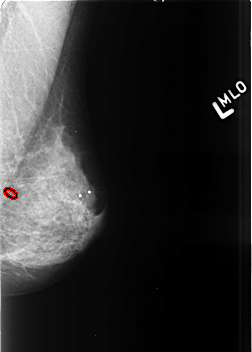

Refer to caption

Normal

Benign

Malignant

Figure 4: Images of Breast Cancer Histopathology from the Mini-DDSM Dataset

Our network is trained and evaluated on three main datasets: BreakHis [4], containing 7,909 breast cancer histopathology images (2,429 benign and 5,429 malignant) at 40×, 100×, 200×, and 400× magnifications, each 700×460 pixels; Mini-DDSM [5], a reduced version of DDSM with approximately 2,000 annotated mammography images detailing lesion locations and diagnoses; and BACH from ICIAR2018 [6], with 400 HE-stained images in four categories (Normal, Benign, In-situ carcinoma, Invasive carcinoma), each 2048×1536 pixels. Fig. 2, 3, and 4 depict sample images from the BreakHis, ICIAR2018, and Mini-DDSM datasets. Tables I, II, and III also present statistical data for these datasets, including sample sizes and class distributions.